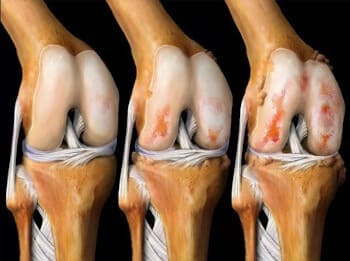

মনে রাখবেন: আর্থ্রাইটিস এবং আর্থ্রোসিস 3 বছরে কার্টিলাজিনাস টিস্যু ধ্বংস করে! দুর্ভাগ্যবশত, আর্থ্রাইটিসের জন্য কোন ওষুধ নেই, শুধুমাত্র একটি অপারেশন আপনাকে সাহায্য করতে পারে...

হাঁটু জয়েন্টের তরুণাস্থির উপর অস্টিওআর্থারাইটিসের প্রভাব।

দুর্ভাগ্যবশত, ডাক্তার ঠিক ছিলেন... দুই মাস পর, দাঁড়ানো আমার জন্য অসহনীয়ভাবে বেদনাদায়ক ছিল, ওষুধ এবং ব্যথানাশক ওষুধগুলি কাজ করা বন্ধ করে দিয়েছিল, যদিও আমি তাদের জন্য প্রচুর অর্থ ব্যয় করেছি, এবং ওষুধগুলি আমার মেরুদণ্ডের জন্য খুব ক্ষতিকর ছিল পাকস্থলী এবং যকৃত: আমাকে তাদের ছেড়ে দিতে হয়েছিল! আমাকে একটি হুইলচেয়ার কিনতে হয়েছিল এবং অ্যাপার্টমেন্টে ঘোরাঘুরি করার জন্য এটি ব্যবহার করতে হয়েছিল... ডাক্তার আমাকে বলেছিলেন যে আর্থ্রাইটিস 3 বছরে তরুণাস্থি নষ্ট করে, তবে এটি আরও আগে শুরু করা উচিত ছিল, মজার বিষয় হল আমি আমার জয়েন্টগুলির মতো অনুভব করিনি খারাপ ছিল, কিন্তু তারপর, হঠাৎ সবকিছু খারাপ হয়ে গেল এবং আমি নিজেকে একটি হুইলচেয়ারে বসে থাকতে দেখলাম, পুনরুদ্ধারের কোন আশা ছাড়াই, আমার মনে আছে আমার চোখ দিয়ে অশ্রু ঝরছিল, এটি ছিল আমার জীবনের সবচেয়ে খারাপ মুহূর্ত...